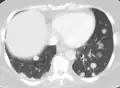

CT image of a lung metastasis -

Metastatic cancer in the lungs -